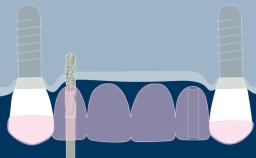

A radiologia é usada em Implantodontia para complementar e confirmar os achados clínicos. As radiografias podem ajudar no diagnóstico, planejamento do tratamento e na revisão de implantes dentários restaurados, em visitas regulares de manutenção. A imagem 3D mostrada aqui demonstra o nível de detalhe que pode ser obtido. No entanto, toda a radiação - incluindo raios-x - acarreta risco de danos aos tecidos e efeitos a longo prazo. Portanto, deve-se considerar os riscos associados à investigação onde a radiografia é planejada, que devem ser equilibrados com os benefícios esperados. Da mesma forma, deve-se considerar uma avaliação das necessidades de diagnóstico e planejamento do caso. A seleção da técnica radiográfica correta deve basear-se no equilíbrio entre as necessidades diagnósticas e o risco.